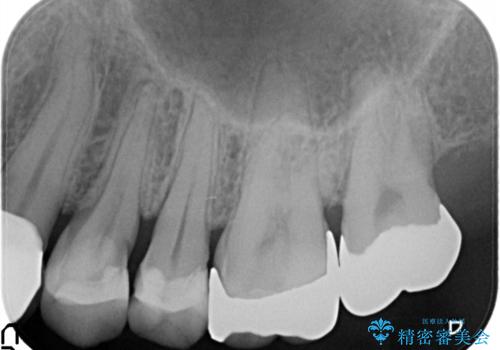

縁下カリエス オールセラミッククラウン

- 以前他院で修復した金属の詰め物の下が虫歯になっており、歯周外科を含めた歯冠修復を行っております。

歯肉縁下の虫歯は精度高い治療を行う場合、歯周外科を提案させていただくことがあります。